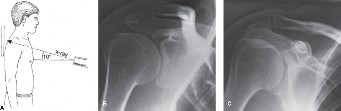

The correct answer is (D). The Zanca view is an AP radiograph obtained by angling the x-ray beam 10 to 15 degrees superiorly and decreasing the kilovoltage (Fig. 2–72A–C). The AP and axillary views should be routinely obtained for investigation of shoulder pathology, but are not the most accurate for AC joint pathology. Stress views have been used in the past to help differentiate type II from type III AC joint instability injuries but are not helpful or indicated in AC joint osteoarthritis. A stryker notch view is used for evaluation of Hill–Sachs lesions of the humeral head after a glenohumeral dislocation.

Figure 2–72A: Zanca view projection. B: AP view of the shoulder that overpenetrates and does not show AC joint well. C: Zanca view demonstrates better ACJ detail. (Reproduced with permission from Shaffer BS: Painful conditions of the acromioclavicular joint. J Am Acad Orthop Surg 1999;7:176–188.)